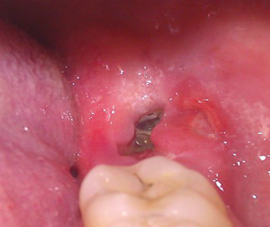

Воспаление зуба мудрости

Перикоронарит

Это самое частое осложнение, связанное с неправильным или неполным прорезыванием зуба мудрости. Характеризуется оно воспалением тканей челюсти, а иногда щеки и слизистой рта.

Как же определить, что развивается перикоронарит?

- не десне появляется сильный отек и покраснение;

- воспаление может распространиться на щеку, висок и даже горло, что вызывает болезненное и затрудненное глотание;

- если отек переходит на мышцы челюсти, это может привести к проблемам в открывании рта;

- самочувствие ухудшается, развивается слабость и поднимается температура;

- при надавливании на десну выделяется гной.